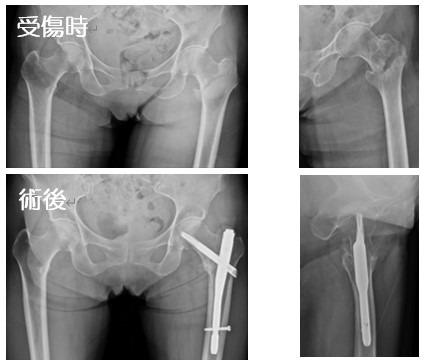

2020-07-21 手外科・外傷 ページ内リンク 髄内釘(short femoral nail) Sliding hip screw 大腿骨頚部骨折(骨接合術) 大腿骨頚部骨折(人工骨頭挿入術) 腿骨転子部骨折(髄内釘) 髄内釘(short femoral nail) Sliding hip screw 大腿骨頚部骨折(骨接合術) 大腿骨頚部骨折(人工骨頭挿入術) 腿骨転子部骨折(髄内釘) 関連ページ 手外科・外傷 一覧へ戻る